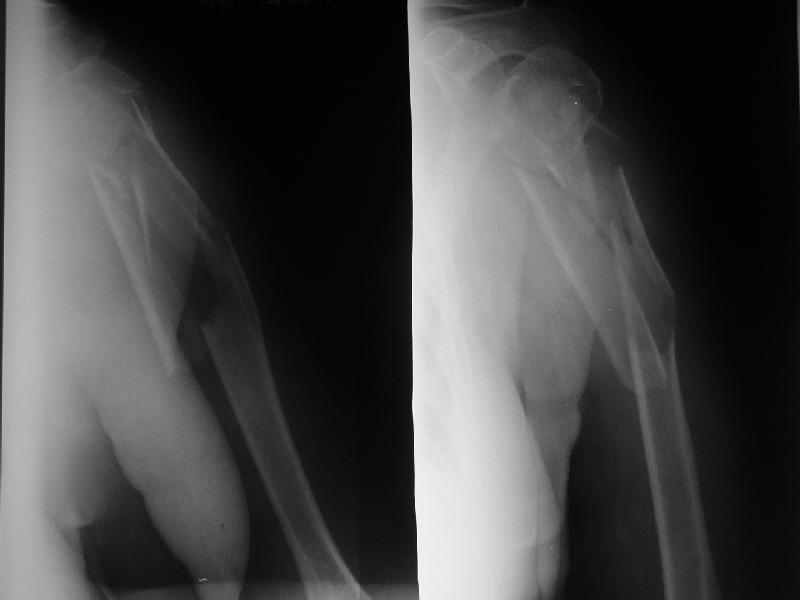

Здравствуйте, уважаемые коллеги. Обратилась пожилая пациентка 60 лет через 2 нед после травмы. Ваше мнение по тактике лечения?

Мы планируем закрытый интрамедуллярный остеоинтез, но к единому мнению пока не пришли.

Если выбор на интрамедулярный штифт, я бы сделал КТ головки, информация необходима для определения вовлечения головки в перелом, имеется опасность

расколочения и для ориентира расположения блокирующих шурупов.

Ув. коллеги. Интересно, насколько разрушена головка, особенно ее артикулирующая поверхность, может для начала сделать КТ головки.

На счет операции - стоит ли ее вообще делать, куда Вы собираетесь забить стержень, на расколете ли головку, если она еще целая. В любом случае Вы